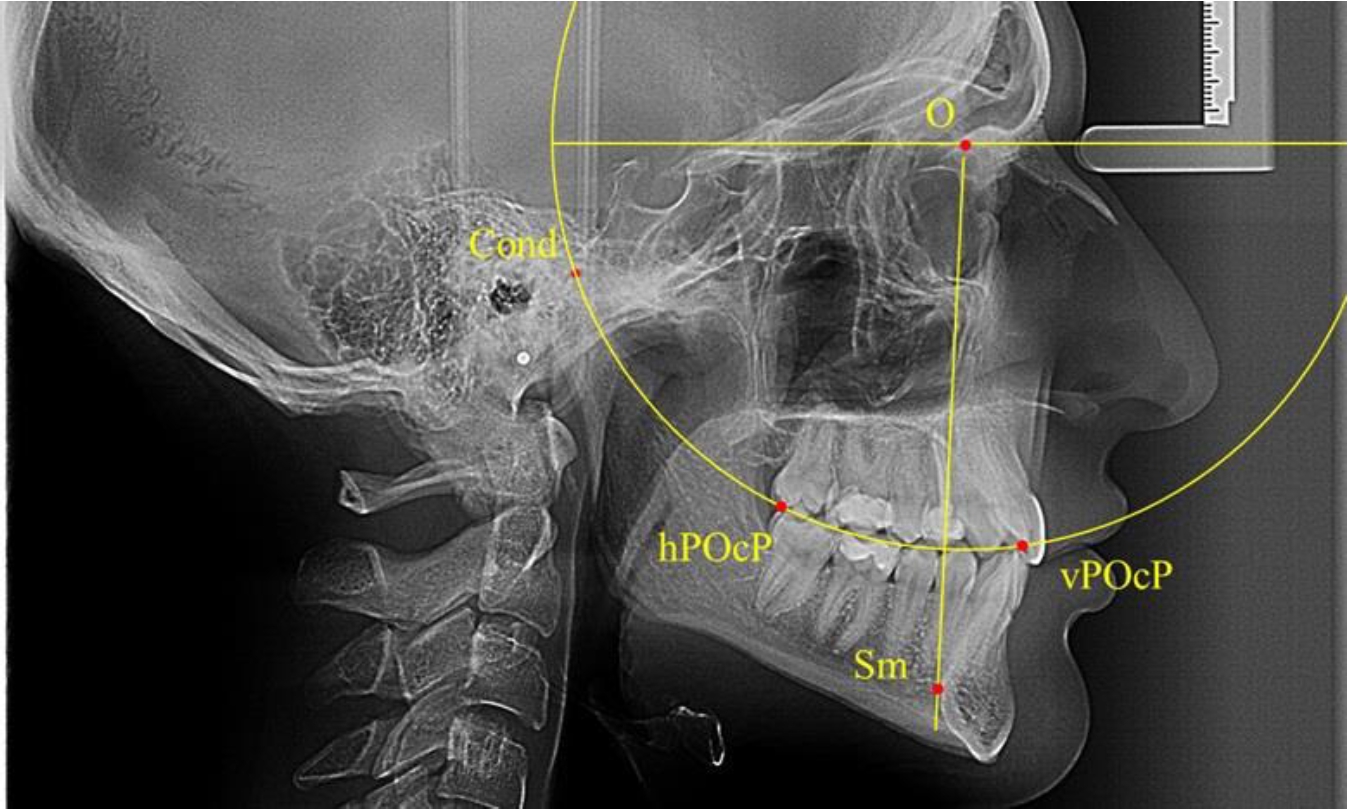

В группе рентгенограмм, выделенных по признаку протрузионного положения резцов, также проводилось распределение на подгруппы с учетом широтных размеров подбородочного выступа.

Анализ результатов показал, что практически при всех вариантах подбородочного выступа в данной группе исследования первые премоляры, как правило, располагались впереди стресс-оси Bimler. Рентгенограммы пациентов с протрузионным положением резцов при среднем и узком варианте подбородочного выступа представлены на рис. 3.

Таким образом, для людей с протрузионным типом зубочелюстных дуг характерно расположение первых премоляров впереди стресс-оси, и этот показатель не может быть использован в качестве выбора метода лечения аномалий для данной группы исследования вне зависимости от формы подбородочного выступа.

Рис. 3. Положение первых верхних премоляров при протрузии со средними (а) и узкими (б) размерами подбородка